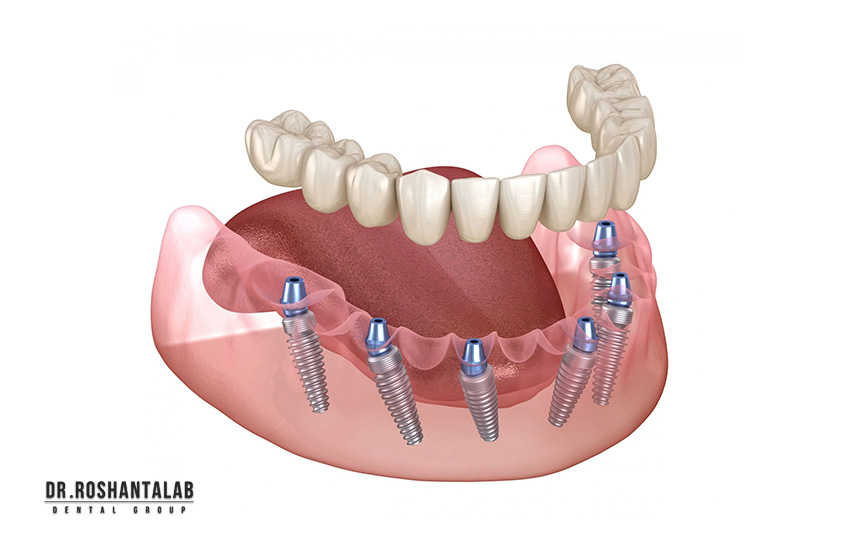

نوع ایمپلنت (مانند اندوستئال، سابپریوستئال یا مینی ایمپلنت) مستقیماً بر قیمت تأثیر میگذارد. ایمپلنتهای دیجیتال و ایمپلنت بدون جراحی (Flapless) که با استفاده از گایدهای سهبعدی انجام میشوند، گرانتر هستند. زیرا نیاز به تجهیزات پیشرفته مانند اسکنر CBCT دارند. ایمپلنت فوری (Immediate Loading) که روکش همان روز نصب میشود، هزینه بیشتری دارد نسبت به روش سنتی که ۳-۶ ماه زمان میبرد. همچنین، ایمپلنت All-on-4 برای فک کامل با ۴ پایه، قیمت کلی را کاهش میدهد.

تعداد دندانهای جایگزینشده مستقیماً قیمت را افزایش میدهد. برای یک دندان، اما برای چندین دندان (مثلاً ۳ دندان) ممکن است تخفیف پکیجی اعمال شود. در موارد فک کامل، روشهایی مانند All-on-6 با ۶ ایمپلنت انجام می شود. تعداد بیشتر ایمپلنتها نیاز به جراحی طولانیتر و مواد بیشتر دارد که هزینه را بالا میبرد.